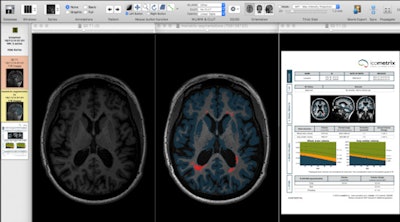

"I believe that we are going in the same direction with MR imaging and that we should consider MR as a lab," he said. "This would allow us to feed the images into a computer and produce a data report showing the exact volume of brain and volume of lesions, with normal range and normal values matched for age and sex."

"At the request of the neurologist, we can feed the data from MS patients into volumetric analysis software to measure the change between scans," he explained. "This is because a new class of disease-modifying medications for MS patients, known as biologics, represents a huge cost burden to society."

Moving on to neuroimaging biomarkers, Parizel noted that two types can be distinguished: cross-sectional and longitudinal. In the cross-sectional approach, we extract and measure volumes in a 3D MRI dataset of a single subject, he explained. The volume of the whole brain, or part of the brain (gray matter, white matter, cerebrospinal fluid, hippocampus, etc.), can be computed through segmentation techniques. These methods rely on segmenting brain tissue from the surrounding scalp and other extracerebral tissues, he continued.

Longitudinal neuroimaging biomarkers take into account two (or more) MRI scans of the same subject, obtained at different time points, to calculate volume changes in brain volume. This enables assessment of MS patients for progressive brain shrinkage (atrophy), a parameter reflecting neuro-axonal and myelin loss, and it is increasingly being used as an outcome measure in MS treatment trials.

Moreover, longitudinal methods for brain atrophy typically match two MRI scans using registration techniques and directly extract small changes in brain volume from this process. A similar approach can be used for the longitudinal segmentation of white matter lesions, according to Parizel.

Biomarkers should help doctors and not generate extra work, Parizel stressed. Radiologists and neurologists don't have time to perform additional postprocessing for every patient, and ideally the postprocessing should be linked to patient informatics, to automatically generate reports that include biomarker information about the lesions and cerebral atrophy.

The radiologist should report back to the neurologist, qualitatively if not quantitatively, about the lesion status and the atrophy of MS patients covering the following: comparison with previous scan(s); evidence of new disease activity; number of new lesions (T2/T1); lesion size; overall assessment, including presence (definite/probable) and extent (number of new/enlarging lesions or gadolinium-enhancing lesions) of disease activity; change in T2 lesion volume; and evidence of brain atrophy, he concluded.